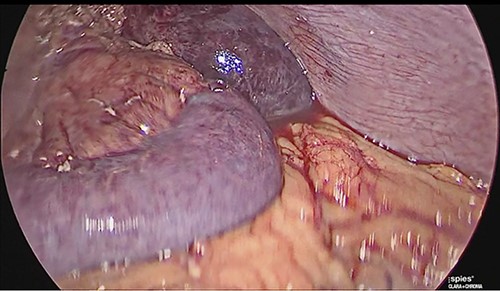

The patient was reoperated by laparoscopy, finding segmental thrombosis from 200 cm to 50 cm of the Treitz ligament, with edema and interloop free fluid without perforation (Figs 3 and 4). Lateral resection and entero–entero anastomosis were performed with manual stapler, subtracting 440 cm of intestine with adequate coloration. Later he was admitted to the Intensive Care Unit, treated with low molecular weight heparin at a full anticoagulation dose, maintaining an INR of 2 and a partial thromboplastin time of 80 s. He presented adequate evolution starting a liquid diet on the fourth postoperative day, new laboratories reported hemoglobin of 11 g/dl, 12 700 leukocytes/mm3, platelets 225 000/mcL, INR of 2. He was discharged on the fifth day with rivaroxaban treatment for 6 months.

Laparoscopic view of intestinal thrombosis and free fluid in the cavity.